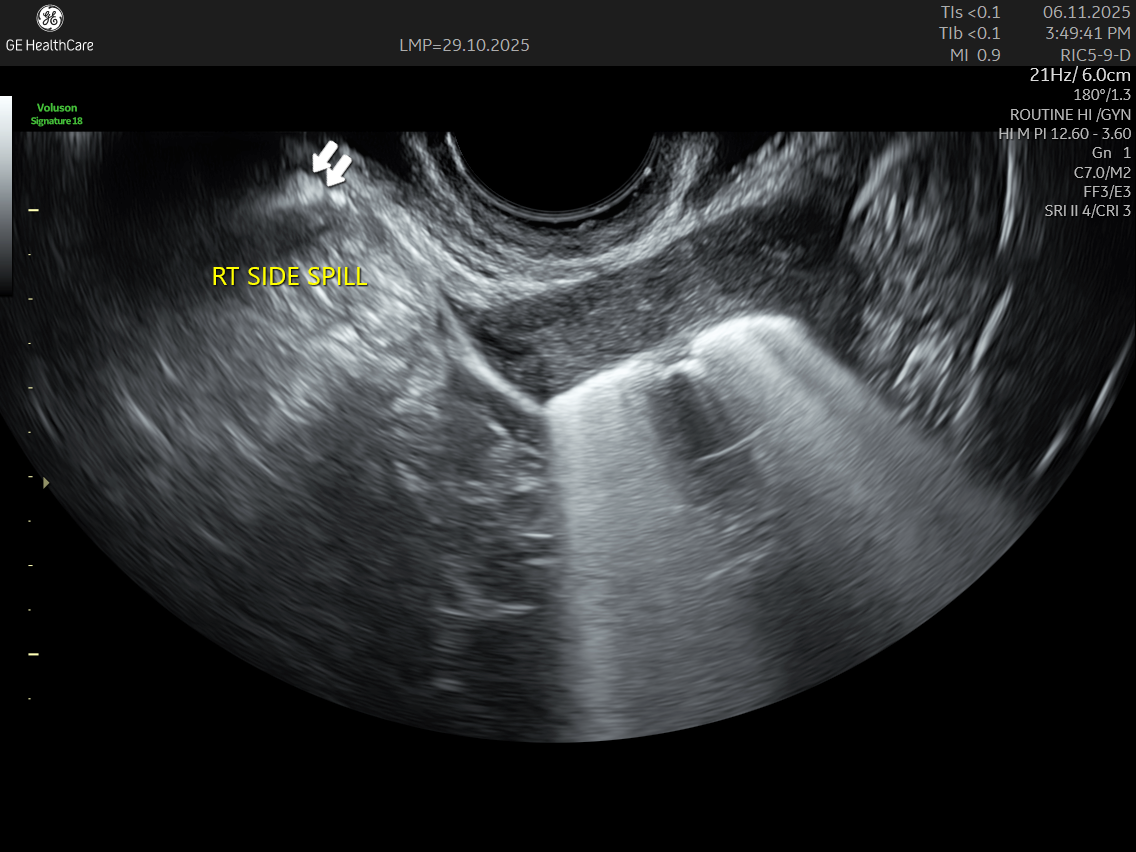

IMAGE GALLERY